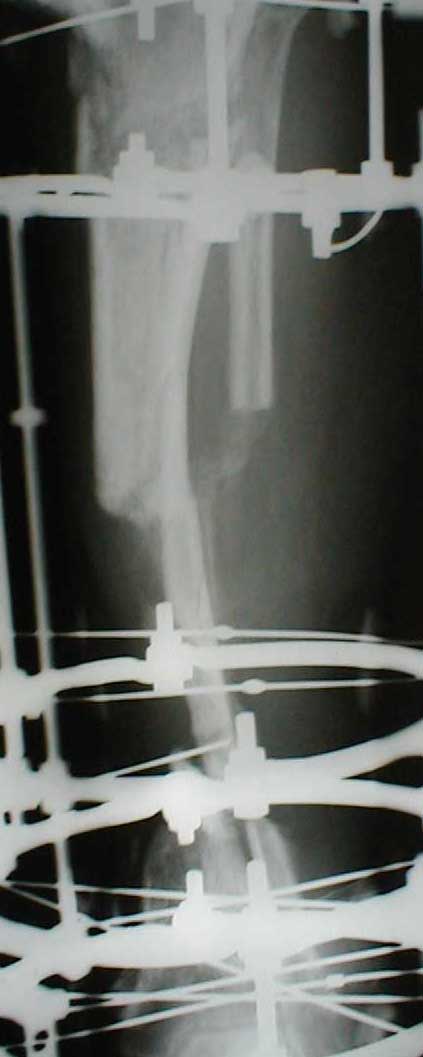

Zdes' snimky posle poslednego montazha apparata prilagaiutsa

Yours Castro

Может быть не совсем в тему, но... Скажите, а чем вызвана такая необычная компоновка аппарата: кольцевидный фиксатор и стержни? На первый взгляд так теряются преимущества монолатеральной стержневой фиксации (легкость перевязок) без достаточной компенсации достоинствами классического ВКДО Илизарова?

Андрей Крылов 02 Июнь 2005, 20:10

"Необычная" фиксация, предполагает осуществление максимальной стабильности проксимального фрагмента б\б кости. Как ее добиться - дело лечащего врача. При всем уважении к монолатеральным фиксаторам, лучше пожертвовать неудобствами при перевязках, чем нестабильностью фрагментов. Если поставлена цель сохранения конечности, то на данном этапе стабильность это - пункт № 1.

Ito vizvanno tem, chto, ja hotil dobitsa bistreshei stabilnoi fiksasii, chto bi dat' sosudestomu hirirgu vozmoznost' rabotat' po medialno-zadnoi poverhonoste, u menjia nibilo dostatochnoe vremjia, dla togo, chto bi provodit' spisy, ih natiagivat' i t.d. i t.p. pre itom ja ni narushal prinsepov vneshnei fikasii dla fixasii poddobnih perelomov. U manjia bili pod rukoi fixatory Hoffmana, i drugie unilateral fixatores, no ja ni stal imi polzovatsa, potomuchto, na moi vzglad', oni malo effectivnie dla dannogo vida povrezdenjia, t.k., oni sozdaiot bol'shoi richag, v rezultate- ita vliaet na stabil'nost', ossobenno v distalnih otdelah, ito kak pravilo, prevodit' k zametnomu oteku nize pereloma, a tut mi smogli provodit'sterzny v teh ploskostiah, kororie nam udobnie v udobnih mestah sobludjia prinsepov "bistro, stabilno, minimalno"

Malo togo, Unilateral frames, ni sposobnie k dalnishemu razvetio, i rano ili pozdno predetsa perehodit' na Ring fixators, tak, chto luche iz nih i nachinat', a voprochem, u kazdego vracha est' vsai vzglady i biomechanicheskie soobrazenjia na opredelennio temu, u opredellnogo bolnogo, i ni vazno kakogo sveta koshky, i vazno chto ona lovit' mish'.